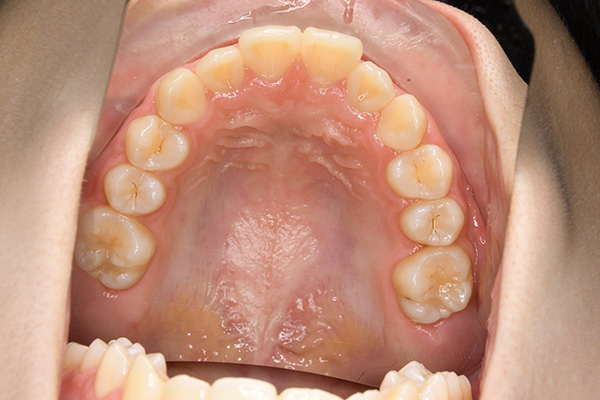

経過観察(13歳10ヵ月)

経過観察

(13歳10ヵ月)

IOP

批評・予后 上顎前歯のアライメントを行ったことで、ロッキングされていた上顎歯槽基底骨の成長に良い影響が生じており、側方歯群の交換も順調に進んでいる症例である。2期治療は相談の上、希望があれば行うこととしている。